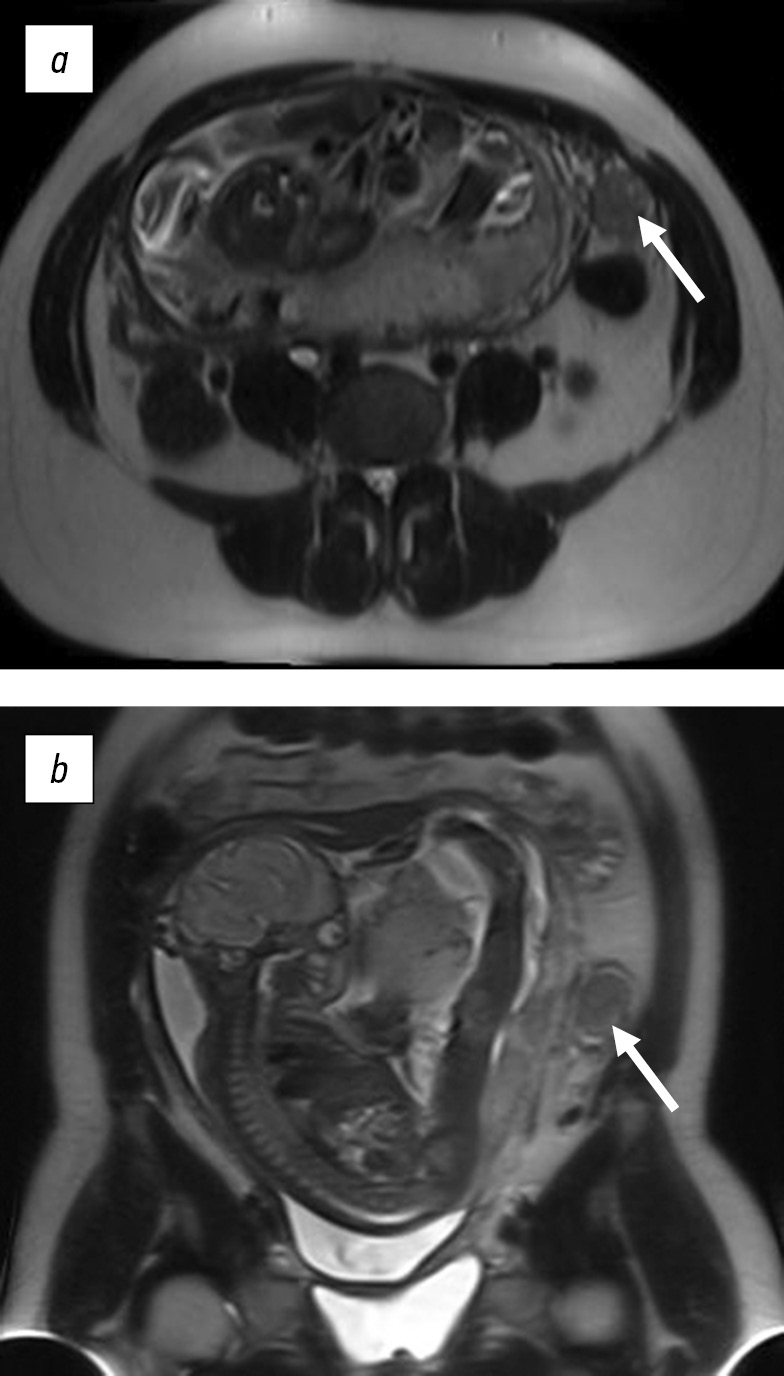

Magnetic resonance imaging (MRI) of the pelvic organs revealed a multi-chamber solid neoplasm of the right ovary with a size of 130 × 90 × 80 mm. In the upper pole of the neoplasm, a cyst was found with multiple thin septa measuring 90 × 70 mm; in the lower pole, a thick-walled cyst was noted with protein content, iso-intensive on T1-WI with a soft tissue component protruding into the cyst cavity up to 12 mm thick, characterized by a hyperintense signal on diffusion-weighted imaging and hypointense on apparent diffusion coefficient. In the central sections of the neoplasm between the large cysts described, multiple cysts of different sizes ranging from 10 to 25 mm in diameter were detected; a pathological soft tissue component was determined in the cysts cavity and between cysts. The left ovary is usually located, with the size of 30 × 20 mm and homogeneous in structure.

Conclusion of MRI indicated a solid-cystic neoplasm of the right ovary (cystadenoma) (Fig. 1).

Fig. 1. Magnetic resonance imaging. T2-WI in coronal (a) and sagittal (b) planes showing a cystic-solid formation of the right ovary (arrow)